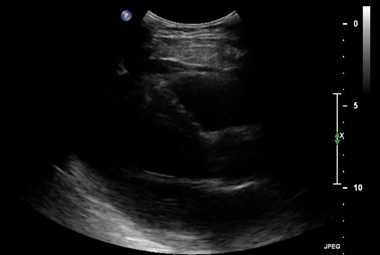

Throughout the case, the patient was managed with total doses of 0.7mg norepinephrine, 9.0mcg epinephrine, 0.4mg phenylephrine, and 23mg dobutamine while using 1L of lactated ringer to maintain adequate blood pressure. Norepinephrine has mixed alpha-1 and beta activity and was used to increase systemic vascular resistance and support myocardial contractility, leading to an increase in blood pressure and cardiac output. Epinephrine has comparable activity on alpha-1 and beta receptors and was used to increase systemic vascular resistance, heart rate, cardiac output, and blood pressure which ultimately provided additional inotropic support. Phenylephrine is an alpha-1 agonist and was given to induce peripheral arterial vasoconstriction, providing improvement in vascular tone and enhancing perfusion pressure.5 During the case, the patient continued to be hypotensive with blood pressures dropping down to 100/40mmHg and dobutamine, a beta-1 agonist with positive inotropic effects, was introduced at 19:38 to enhance cardiac output by increasing myocardial contractility.5 The thrombectomy was completed uneventfully and tolerated well by the patient (Figure 1-3).

Figure 3 Lung ultrasound demonstrating the presence of multiple B-lines (vertical hyperechoic artifacts extending from the pleural line to the bottom of the screen). B-lines are a sign of increased extravascular lung water and pulmonary edema, which are common findings in patients with acute heart failure. The increased number and diffuse distribution of B-lines throughout the lung fields suggest a significant degree of pulmonary congestion secondary to the patient's cardiac dysfunction.